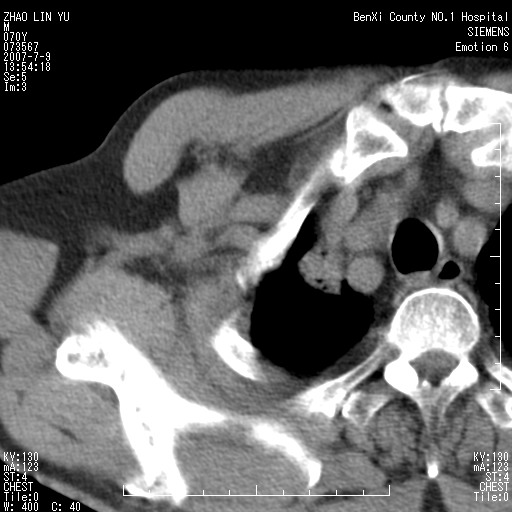

以下是引用王靖旗在2007-7-10 17:12:00的发言:[br] 男、70、咳嗽两个月,半年前换瓣手术,胸片未见异常,于昨天行x片发现右肺上野大片影,行ct扫描,这里是减薄图像,余肺正常。明天晚上会有增强扫描片,到时我会上传。[br][br] 冠状位请大家细看,应该是有意义的,[br][br] 请大家先看平扫发表意见。[br][br]

[br]冠状面[br]

以下是引用zhangzhongshou在2007-7-10 21:43:00的发言:[br]右肺上叶周围型肺癌,以孤立型细支气管肺泡癌可能性大。